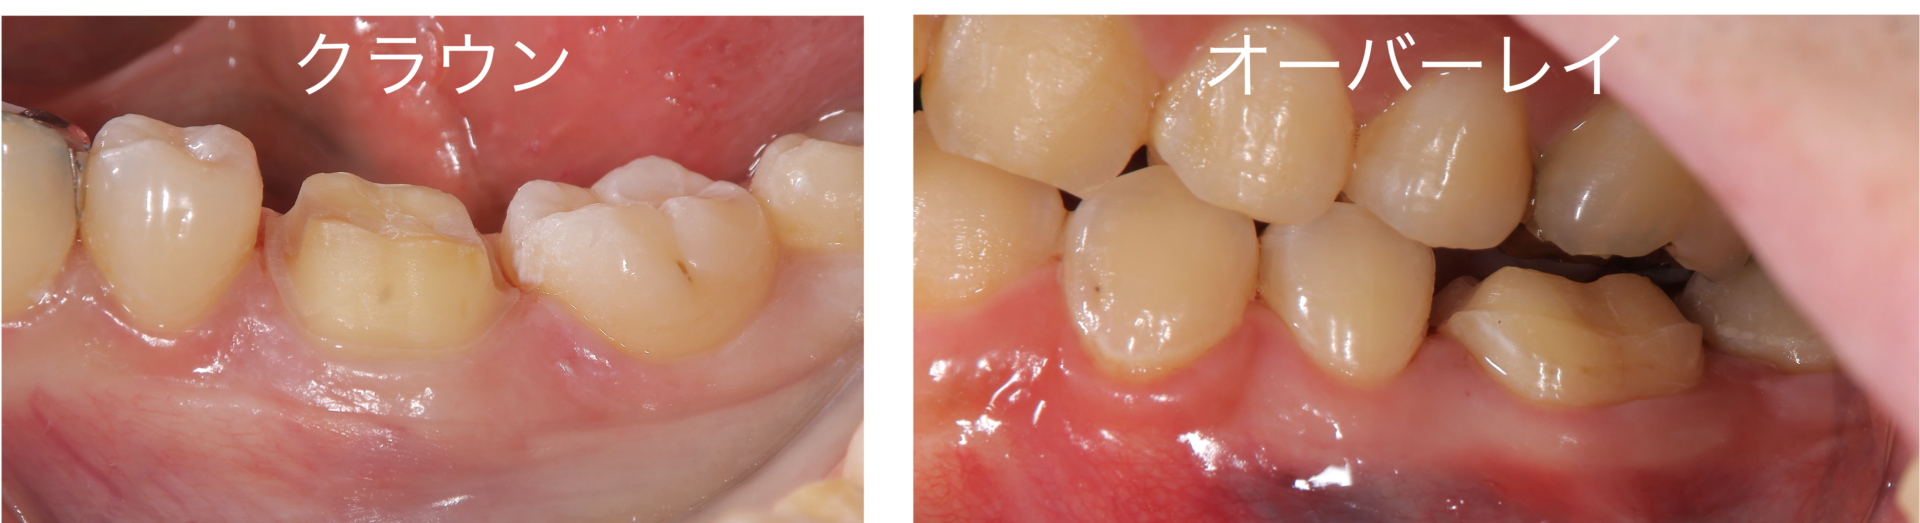

本日は、虫歯治療や根の治療が終わった後の治療の選択肢をお話させていただきます 従来から存在する治療の選択肢(被せもの、クラウン) 虫歯が大きい歯や、神経をとって根の治療が終わった後に、「被せ物(クラウン)で治療をしましょう。」と歯医者さんに言われた経験はございませんでしょうか? 被せ物(クラウン)は、従来より用いられてきた治療方法ではありますが、被せ物(クラ …